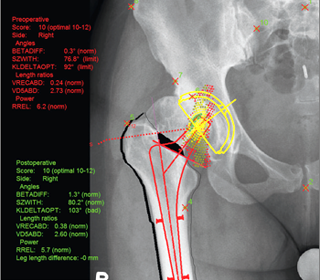

mediCAD® tự động đề xuất phương án tối ưu vị trí của điểm trung tâm dựa trên thông số của kích thước cơ thể, trọng lượng và phân tích sinh trắc học ban đầu.

Việc tái phân phối trọng lực được đánh giá và độ đàn hồi sinh lý của cơ được mô phỏng sử dụng tiêu chuẩn sinh trắc học giúp đánh giá độ bền vững của khớp nhân tạo. Phần mềm cũng đưa ra lời tư vấn về lựa chọn thiết kế hình dạng khớp nhân tạo tối ưu tránh các kết quả xấu do bất tương xứng về cơ sinh học gây ra.

Phần mềm có các khả năng độc đáo để trả lời những câu hỏi ở trên. mediCAD® tính toán và hiển thị tâm xoay thích hợp với thiết kế khớp tối ưu, mô phỏng khả năng chịu tải của một khớp háng khỏe mạnh. Tâm xoay được tối ưu hóa về mặt toán học nằm trong vùng màu xanh lá cây, đặt nó ở vị trí tối ưu trong phạm vi thang 12 điểm. Phần vỏ trong của thân xương được tự động nhận diện để ăn khớp chính xác với chuôi khớp nhân tạo.